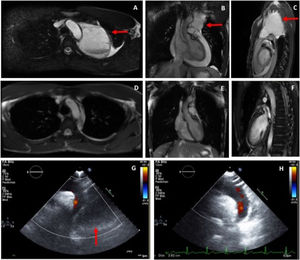

Cardiac magnetic resonance (CMR) was performed and showed, adjacent to the predominantly superior pericardial effusion, a thin-walled cyst in the mediastinum measuring 7.6×7×9.7 cm (figure 2A-C) whose content had a signal intensity higher than that of the pericardial effusion, indicative of higher protein content. On prone sequences, both the pericardial effusion and the pleural fluid displaced anteriorly, while the cyst remained in a posterior position. The findings indicated acute pleuropericarditis with a pericardial cyst of atypical location.

Pericardial cyst (arrows) on cardiac magnetic resonance on axial (A), coronal (B), and sagittal (C) views. Cardiac magnetic resonance at one month post-discharge showing complete resolution; axial (D), coronal (E), and sagittal (F) views. Echocardiogram on suprasternal view on admission (G: with pericardiac cyst, arrow) and at 1 month after resolution (H).

After improving clinically, on blood tests, and radiologically (figure 1C), the patient was discharged. However, due to the persistence of the pericardial cyst, he was referred to thoracic surgery for assessment for invasive treatment. CMR performed at 1 month showed complete resolution of the pleural effusion, pericardial effusion, and associated cyst (figure 2D-F), making surgical treatment unnecessary.

Unlike cysts, pericardial diverticulae freely communicate with the pericardial space, which can be identified by changes in the shape and size with changes in position or with respiration.6 In the case presented here, although some of the CMR projections suggested a degree of connection between the cyst and the pericardial space, there did not appear to be an open communication that allowed passage of fluid. The unchanging size of the pericardial mass with postural changes, the higher intensity of its content compared with the pericardial effusion (characteristic of pericardial cysts6) and its persistence after the pericardial effusion had completely resolved made us lean toward a diagnosis of pericardial cyst.